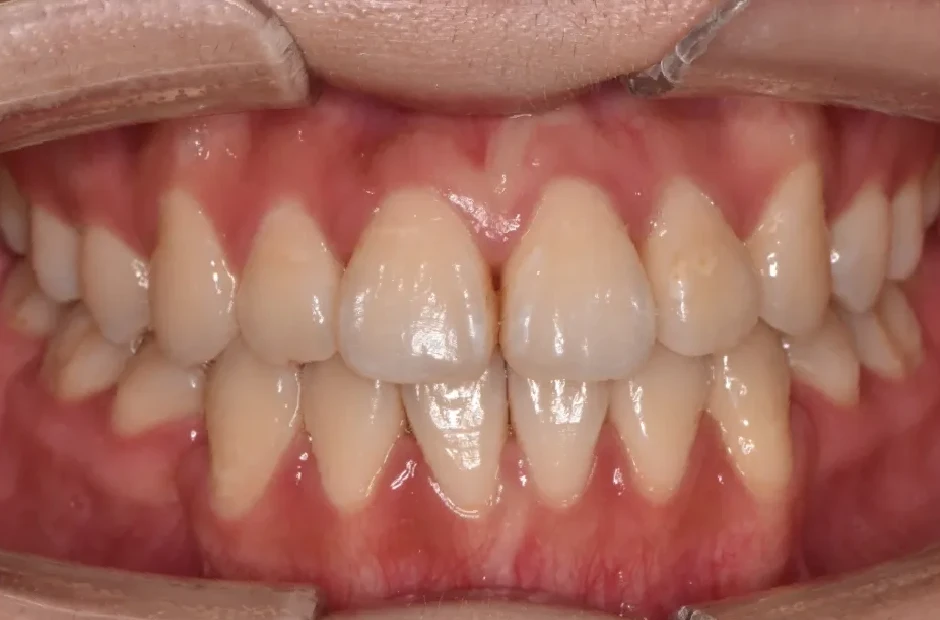

叢生

| 診断名・主訴 | 叢生 |

|---|---|

| 年齢・性別 | 43歳・女性 |

| 治療期間・回数 | 2年7か月 27回 |

| 治療に用いた主な装置 | 舌側矯正 |

| 抜歯部位 | 両顎4,4 |

| 治療費 | 100万円(税抜) |

| リスク・副作用 | 装置による違和感・疼痛・歯肉退縮・歯根吸収・虫歯のリスクなど |

治療後